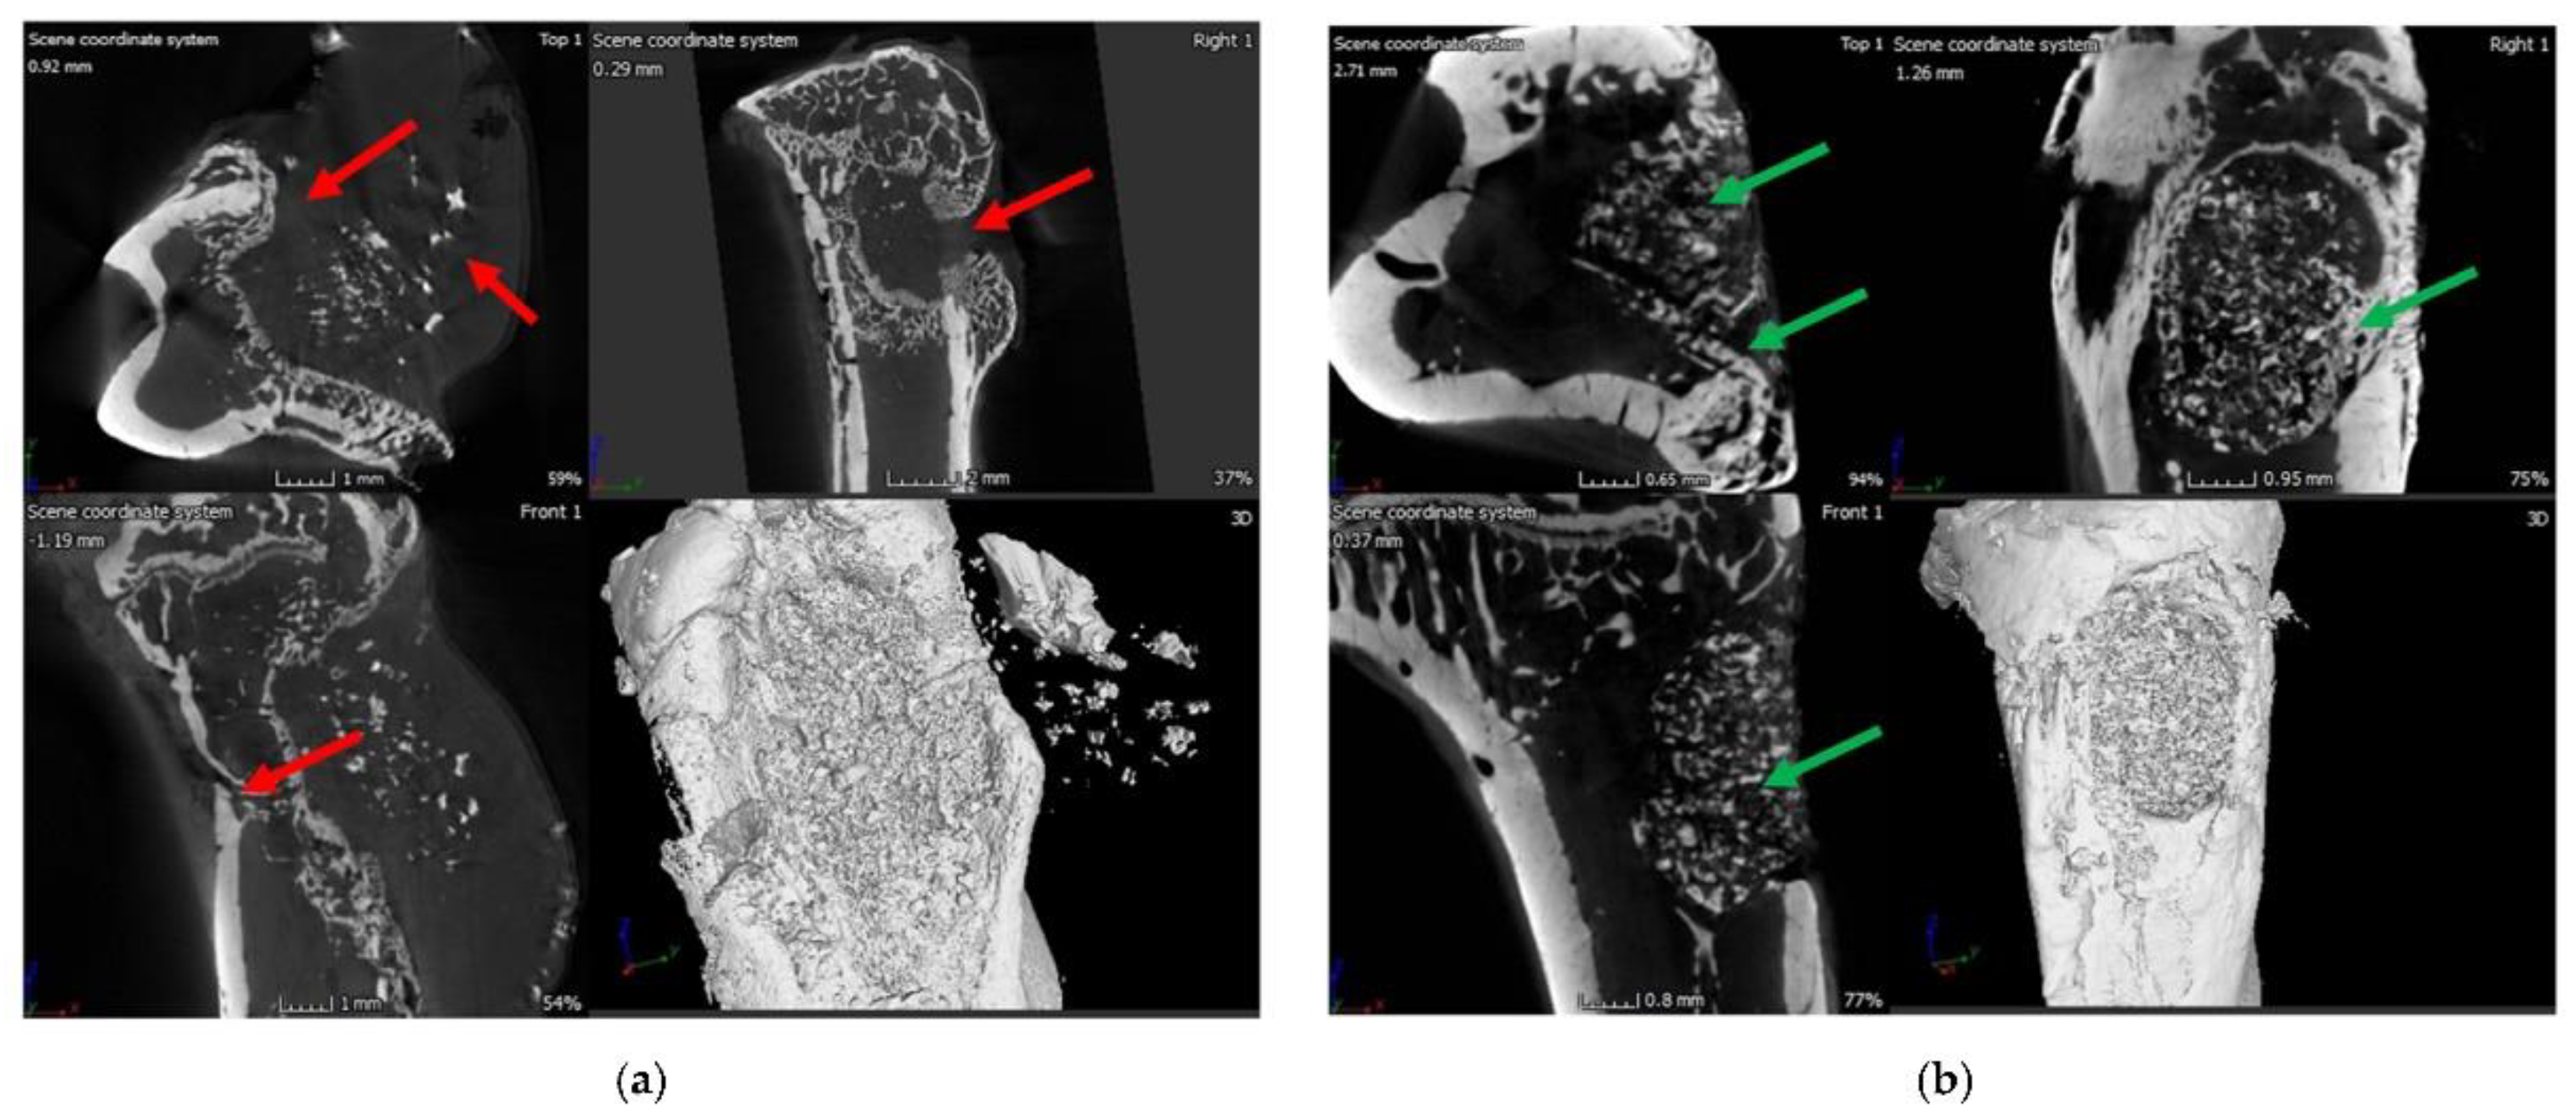

- Duta, L.; Neamtu, J.; Melinte, R.P.; Zureigat, O.A.; Popescu-Pelin, G.; Chioibasu, D.; Oktar, F.N.; Popescu, A.C. In vivo assessment of bone enhancement in the case of 3d-printed implants functionalized with lithium-doped biological-derived hydroxyapatite coatings: A preliminary study on rabbits. Coatings 2020, 10, 992. [Google Scholar] [CrossRef]